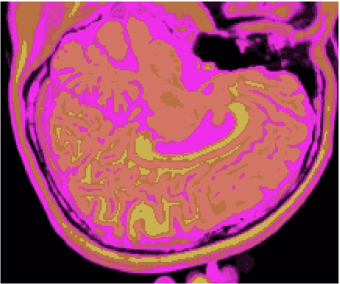

Figures 1 (band 0), 2 (band 1) and 3 (band 2) show PD- (proton density), - and -weighted MR images of the 97th slice, while figure 4 shows the R0-G1-B2 colored composition of the same slice.

Figures 5, 6, 7 and 8 show classification results, whilst figures 9, 10, 11 and 12 exhibit quantization results for the image of the 97th slice, figure 4, using methods KO, CM, KM and ODC, respectively. Image quantization is the procedure of constraining a determined image from its complete set of pixels to a smaller set of vectors with same dimensions feasible to represent the original image with a smaller gamute, according to a given fidelity measure. Herein this work we built quantization images just by changing the original pixels for the vectors of weights related to the classification results, i.e. the centroids of the unsupervised classification methods.